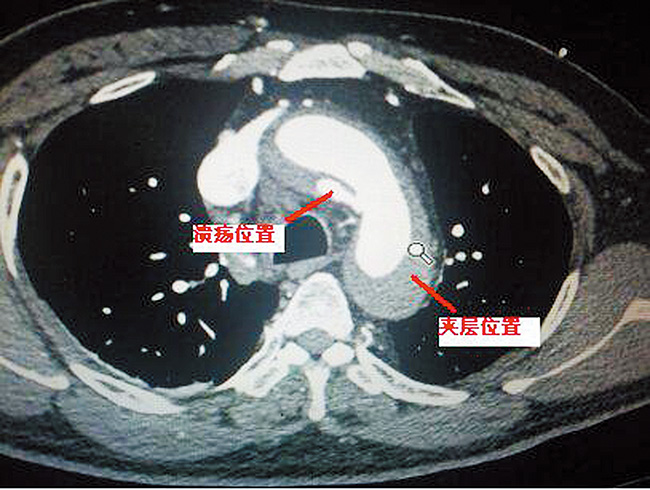

2014年12月4日心脏大血管外科为一名主动脉巨大溃疡合并B型夹层的患者,成功实施腔内隔绝手术(左颈总动脉和左锁骨下动脉双开窗),术后造影显示:左颈总动脉和左锁骨下动脉通畅良好。夹层、溃疡消失,无内漏。查询,双开窗技术在腔内隔绝手术治疗夹层应用中,是河南省首例。该项手术的成功开展,开创了心脏外科高难度介入手术的先例,继去年我科为B型夹层(破口靠近左锁骨下动脉),行左锁骨下动脉单开窗技术,又上了一个新台阶。

该患者男性,47岁,患者主诉胸背部疼痛3小时。主动脉CTA提示:主动脉夹层(主动脉弓部小弯侧穿透性溃疡形成合并B型夹层)。由于患者溃疡位于做左锁骨下动脉下方小弯侧,传统方法,封闭左锁骨下动脉或采用“烟囱”技术,容易使患者术后头痛左上肢活动耐量下降,内漏发生律高。南阳市中心医院心脏大血管外科杨侃主任聚集科室精英骨干,讨论病案,决定突破了传统手术方法,采用介入双开窗技术手术,在导管室全麻下行主动脉腔内隔绝术,支架前端0.5cm向后开一3x1cm窗,术中支架紧贴无名动脉远端释放,开窗部位与左劲总动脉左锁骨下动脉精确对位。术后溃疡完全封闭,头臂血管血流通畅,假腔消失。本例介入手术,突破了传统手术方法,取支架开窗手术优点,避免了封闭左锁骨下动脉及烟囱内漏等传统弊端。